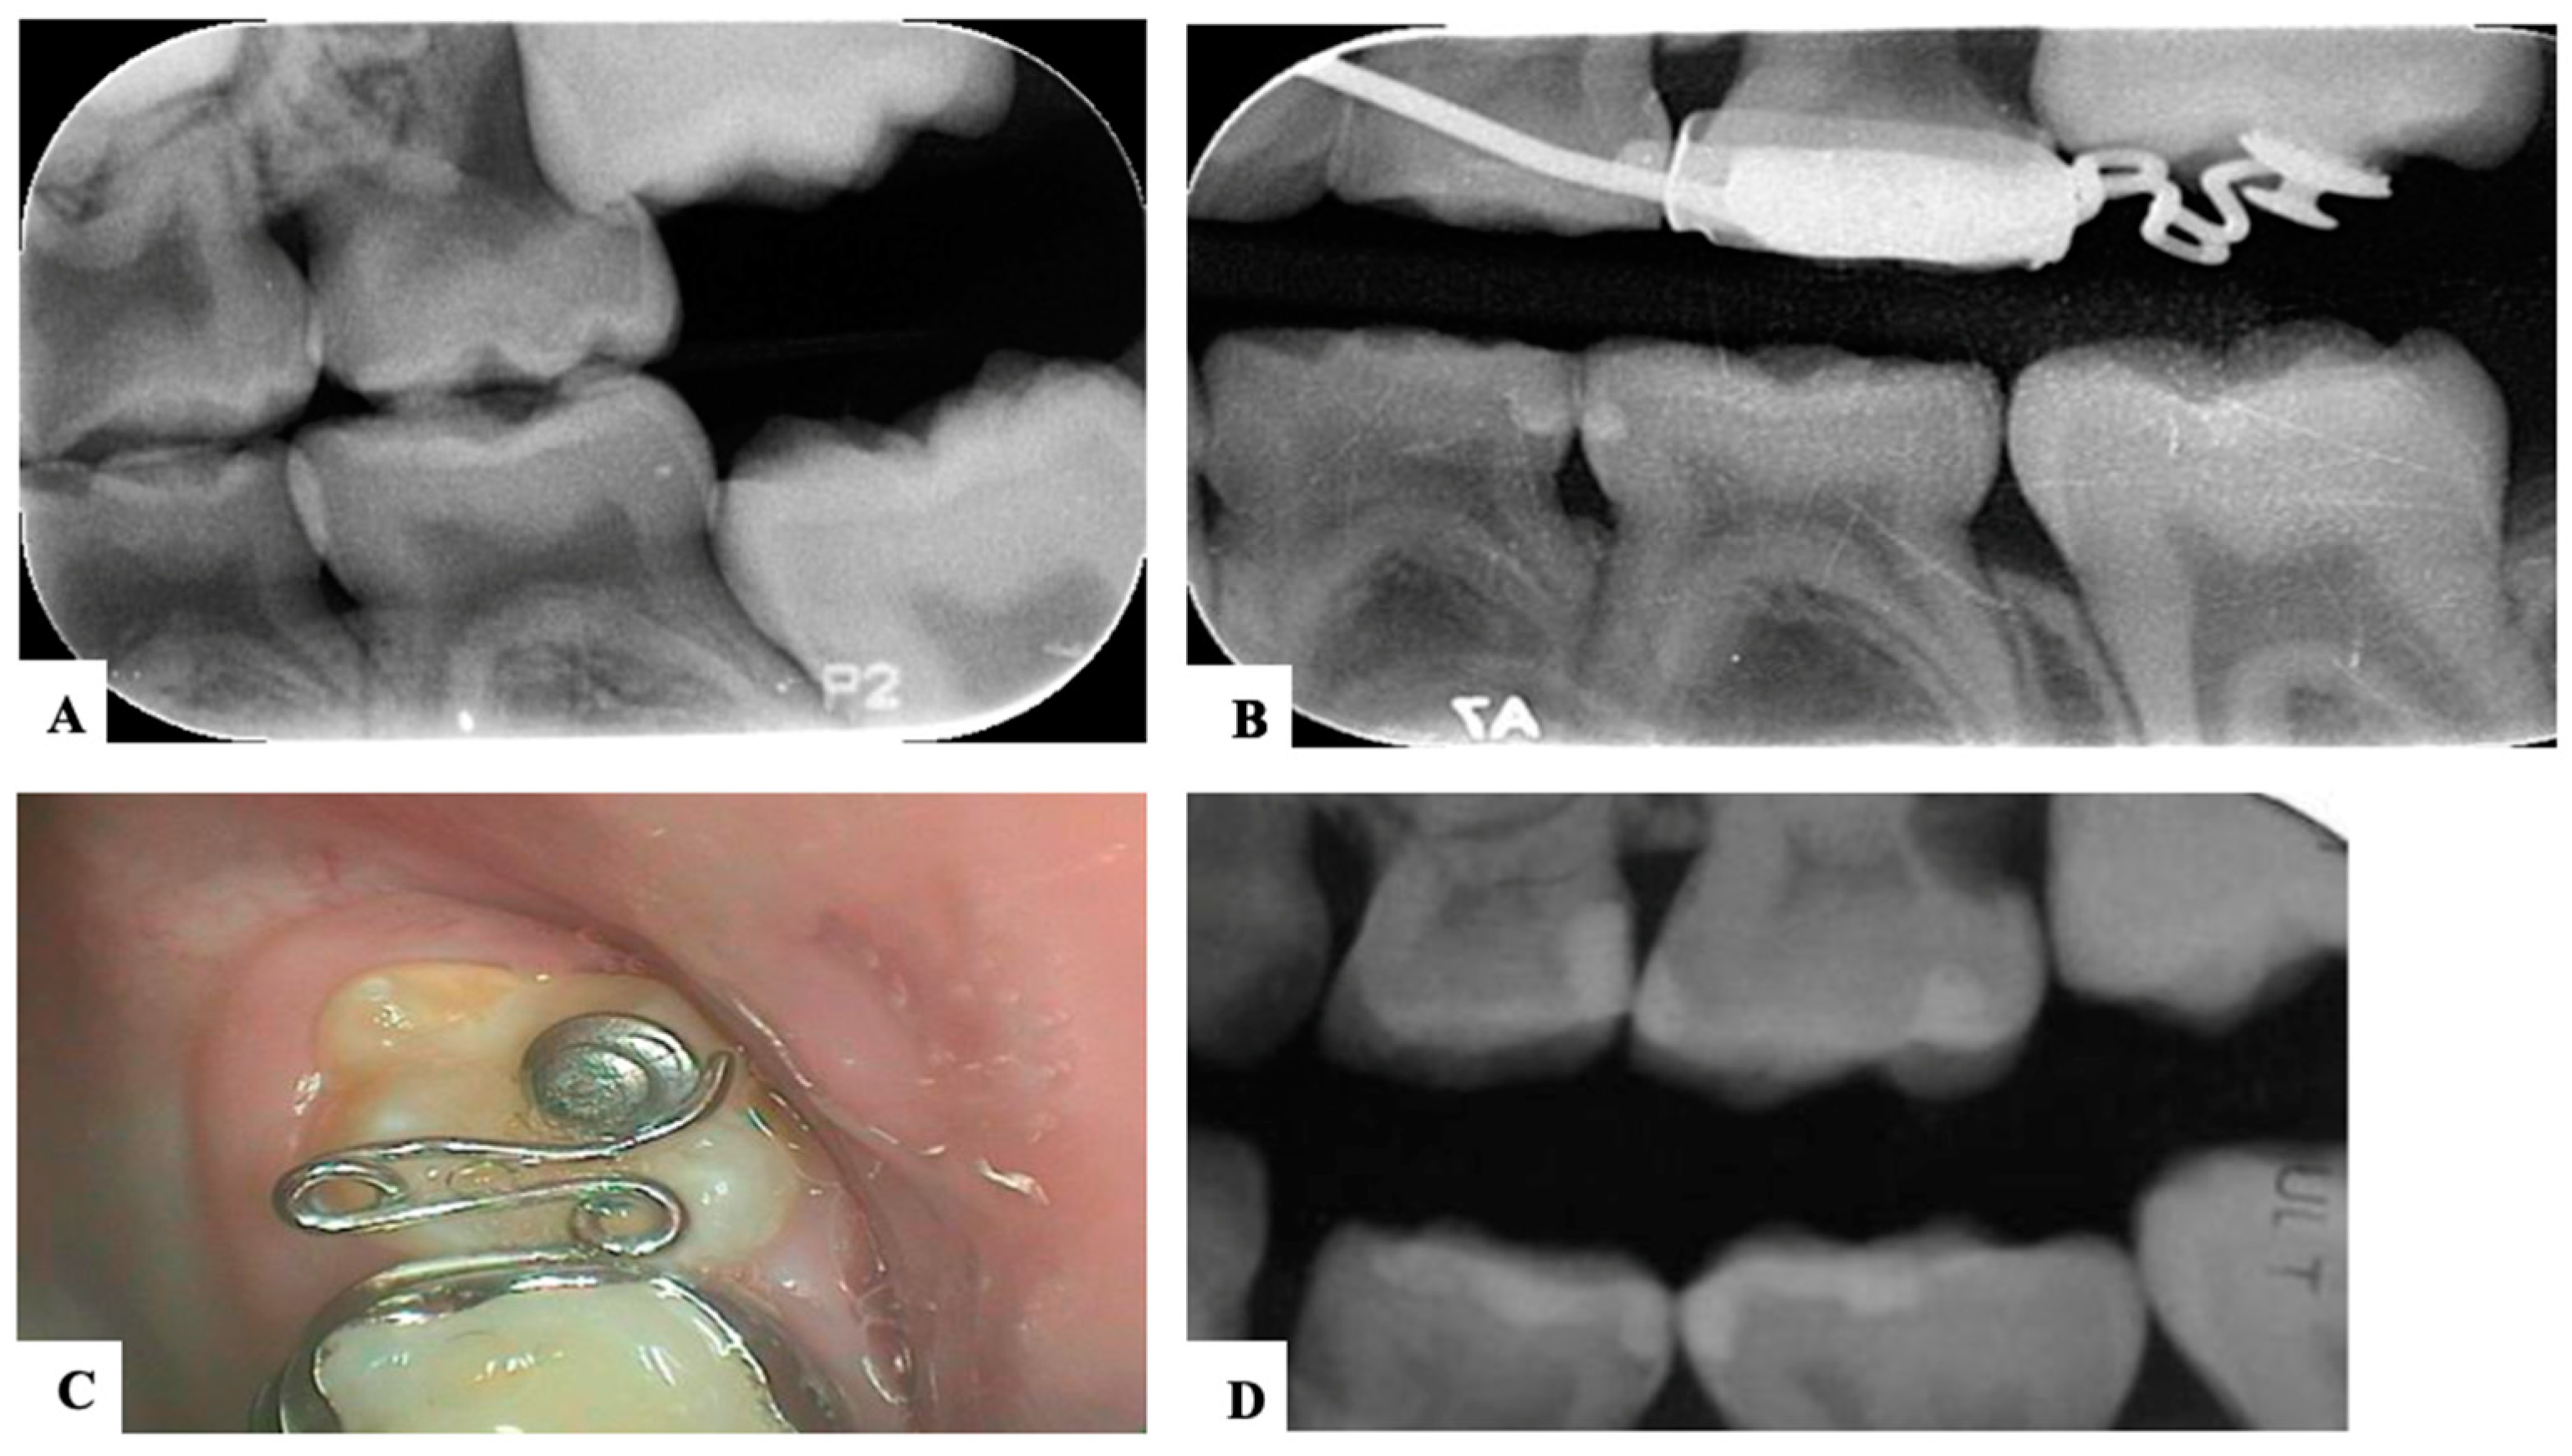

| Harrison and Michal’s Classification (based on severity of the lock using bitewing radiograph) * | |||||

| Normal | Minimal lock | Severe lock | |||

| No sign of impaction | Impacted less than half the width of the distal marginal ridge of the second primary molar | Impacted more than the width of the distal marginal ridge of the second primary molar | |||

![]() | ![]() | ![]() | |||

| Treatment Modalities | Severity of Impaction | Chair Side Time | Laboratory Work | Patient Discomfort | Cost | Treatment Duration |

|---|---|---|---|---|---|---|

| Elastic separator [35] | Mild to moderate | ↓ | ✕ | ↑ | ↓ | ↓ |

| Soft brass wire separator [37] | Mild to moderate | ↓ | ✕ | ↑ | ↓ | ↓ |

| Spring separator | Mild to moderate | ↓ | ✕ | ↑ | ↓ | ↓ |

| Humphrey appliance | Moderate to severe | ↑ | √ | ↓ | ↑ | ↓ |

| Halterman appliance [35] | Moderate to severe | ↑ | √ | ↓ | ↑ | ↓ |

| Croll’s appliance [4] | Moderate to severe | ↑ | √ | ↓ | ↑ | ↓ |

| Fixed edgewise appliance | Moderate to severe | ↑ | ✕ | ↓ | ↑ | ↓ |

| Surgical uprighting | Severe | ↑ | ✕ | ↑↑ | ↑↑ | ↑ |